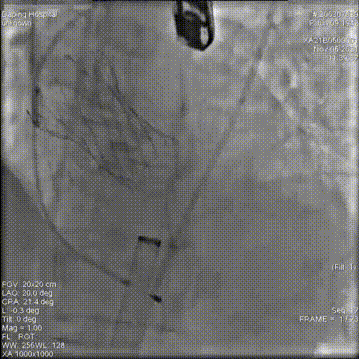

主动脉根部造影

18mm球囊预扩

第一次释放,位置过高回收定位

第二次释放,位置过低再回收释放

第三次瓣膜释放定位

23mm瓣膜释放中

20mm球囊后扩前造影

术后造影

术后压差14mmHg,钙化一侧微量反流,瓣膜正常工作,血流动力学即刻得到改善。